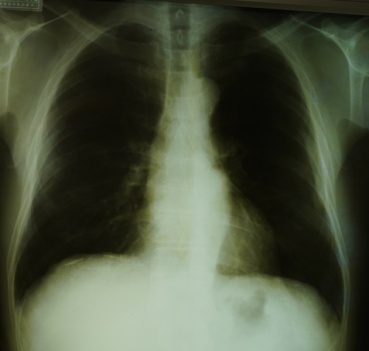

2. 職業ばく露 建設業

1995年から2017年まで建設国保組合と連携して1万~4万人の胸部レントゲン写真を読影してきた。2000年段階での読影結果を示した【図3】【図4】。

建築の労災事案の経過についての研究は、1998年から2012年11月までの14年間を、石綿肺管理2以上続発性気管支炎の合併症で療養した25名で観察した7)。結果は、

(1)観察期間の中央値は10(最短4~最長14)年で、14年間に死亡した者15名、現在当院通院中が10名であった。死亡した15名の死亡診断書の死因は、原発性肺がん6名、慢性呼吸不全6名(在宅酸素療法から呼吸不全死亡)、続発性気管支炎+肺炎が2名、間質性肺炎(UIP疑い)1名であった。胸部CT写真の読影では24名に、胸膜プラーク(医師3名一致20名、2名一致4名)が認められた(35.8%)。胸部CTの点状陰影(DOT’S陰影)密度増加は、4名(医師3名一致は1名のみで、医師2名一致が2名、医師1名指摘が1名)と判断が分かれた。【写真4】